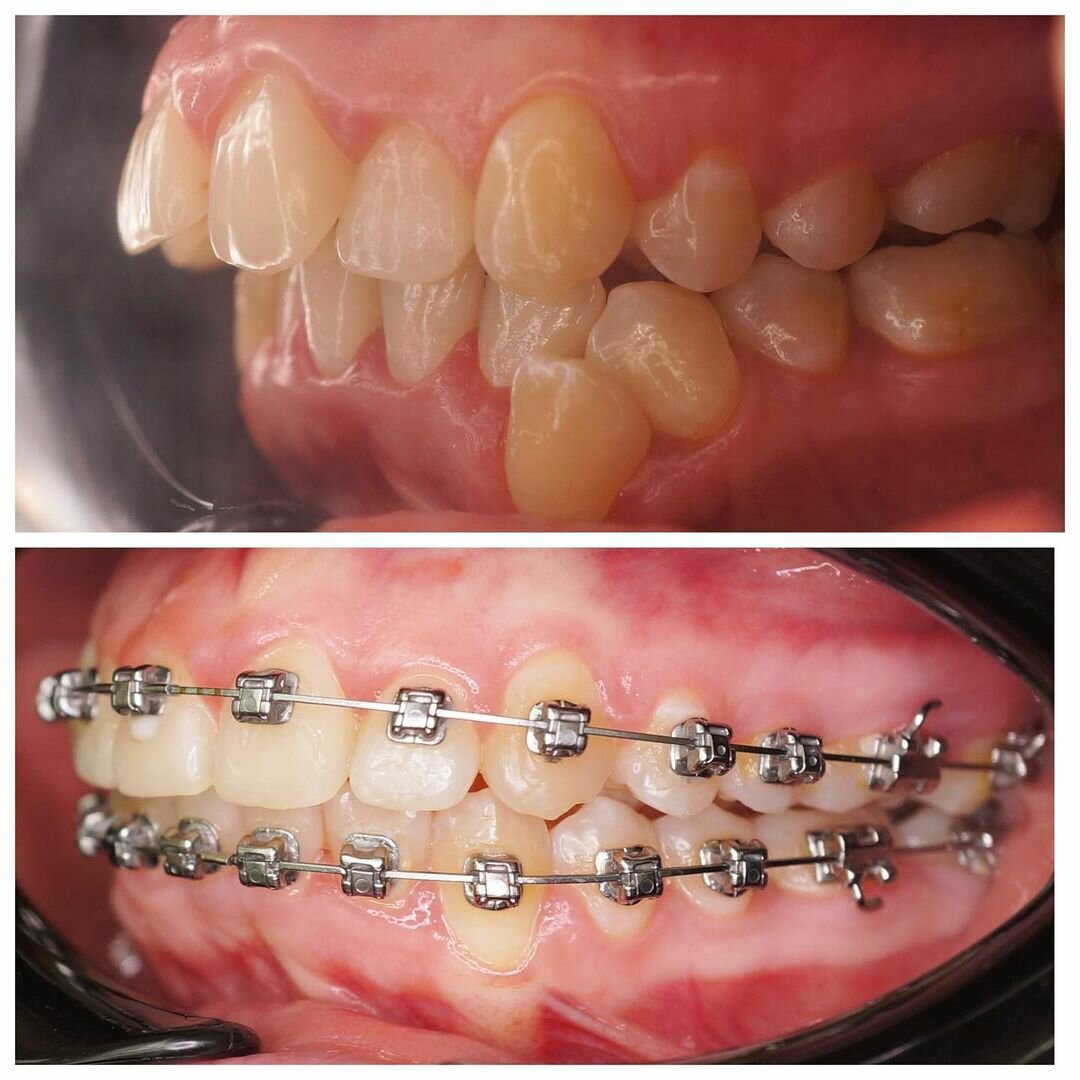

- ортодонтия

- брекеты

Gold Dent специализируется на различных направлениях стоматологии: общей терапии, хирургии, ортодонтии, эстетической и детской стоматологии, имплантологии, протезировании и эндодонтии. В клинике применяются передовые технологии, такие как цифровая стоматология CAD/CAM, лечение под микроскопом, компьютерная томография и костная пластика.